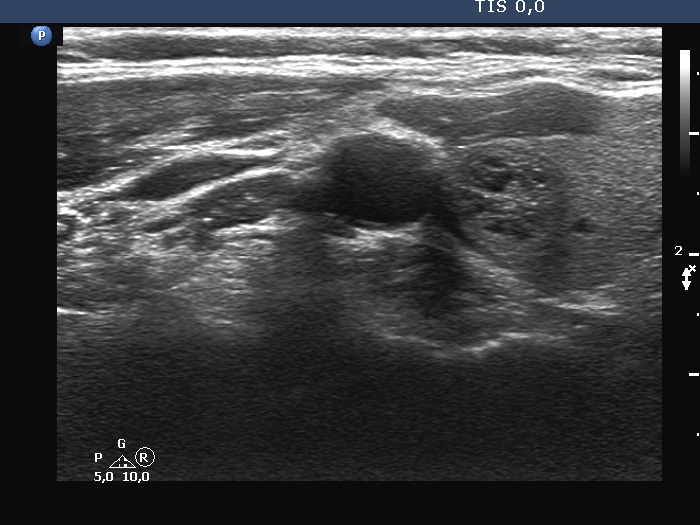

The shape of the nodule - case 1257 (ultrasonographic picture 2)

Right lobe, another transverse scan.